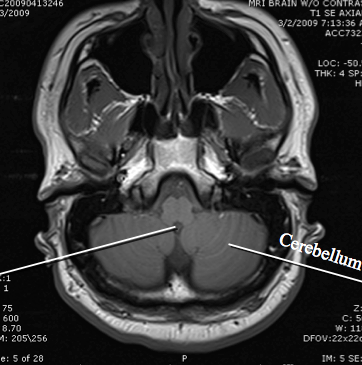

hypothalamus

cerebral aqueduct

cerebellum